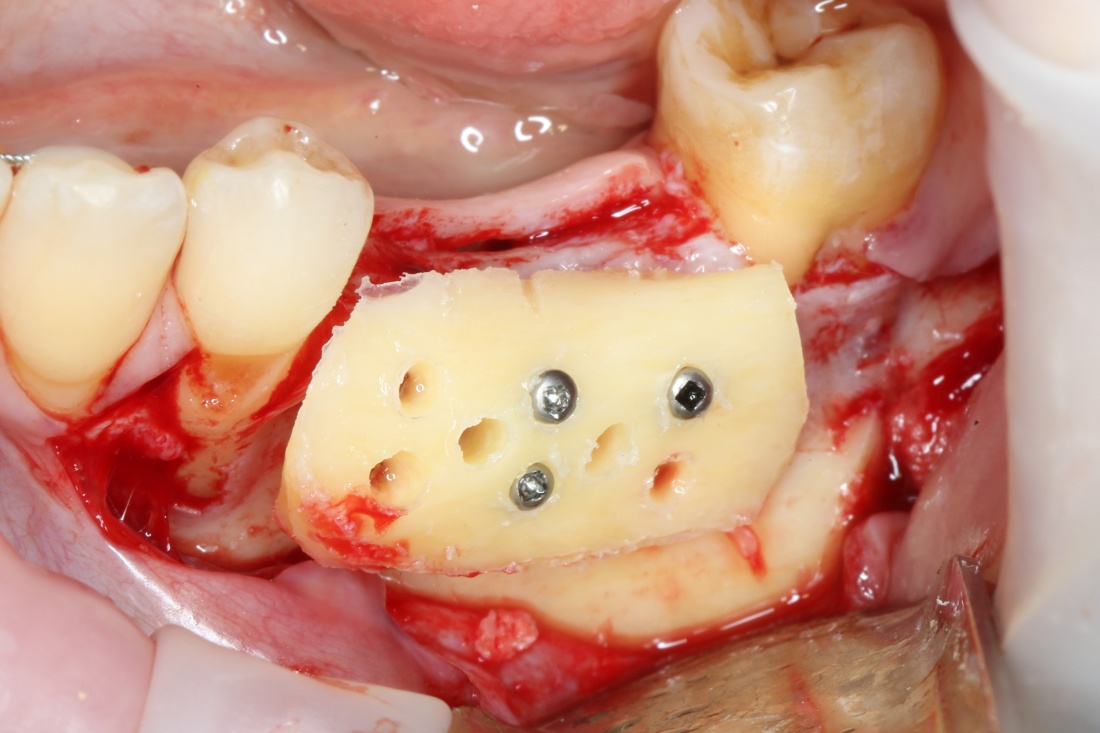

Далее, примеряем и адаптируем костный блок:

A09A5449 (2) A09A5450 (2)

Готовим его к фиксации:

A09A5451 (2)

Многие ошибочно предполагают, что большое количество дырок в блоке нужно для того, чтобы «всё лучше срослось». На деле, большое количество отверстий в аутокостном фрагменте даст нам возможность переставлять вины и адаптировать его «на месте». А это особенно важно для одномоментной установки имплантов, потому что винты не должны попасть в проекцию будущей лунки.

Фиксация костного блока:

A09A5452 (2) A09A5453 (2)

Для этого стоит использовать длинные винты. В противном случае, при подготовке лунки под имплантат костный блок может отлететь.